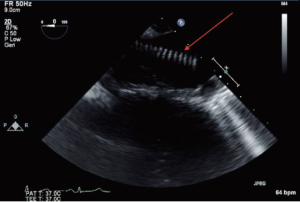

Localization of the elephant trunk graft in the descending aorta is made by transesophageal echocardiography and epi-aortic ultrasound (Figure 12). After the distal aorta is clamped, left atrial to femoral bypass is instituted, adenosine is administered for cardiac standstill (16 mg) and a vertical aortotomy is done in the descending aorta at the level of the elephant trunk graft, which is then retrieved by the finger-thumb technique. After digital retrieval of the graft, the elephant trunk is clamped (Figure 13). We like to quickly place an initial clamp on the elephant trunk for hemostasis (the patient can quickly exsanguinate). However, the graft is often folded longitudinally on itself. With the initial clamp in place, we readjust and place a new clamp squarely, without any folding of the graft, above the original clamp, which is then removed. It is now important to pull down gently on the elephant trunk, as a considerable longitudinal portion of the elephant trunk graft may still be up in the aortic arch. Without “pulling down” the free upper portion of the elephant trunk, the eventual completed graft, after distal anastomosis, will be too long and thus susceptible to kinking.